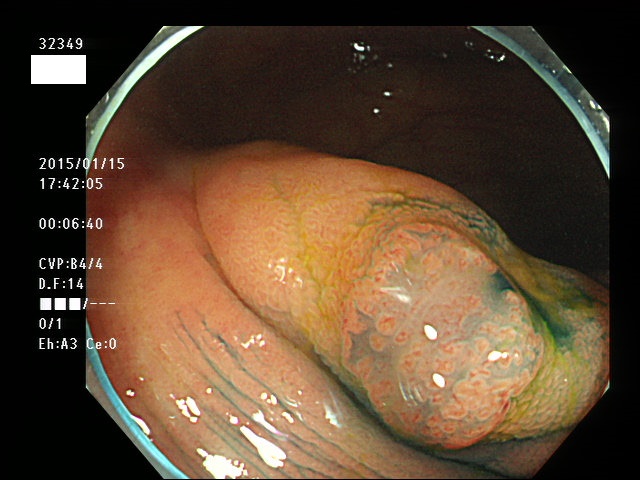

上記100名より抽出した平坦・陥凹型腺腫(=癌化の危険が高いが見落としやすい病変)の内視鏡写真

32300 32301(SSA/Pのみ) 32302(SSA/Pのみ) 32304 32306 32308 32309 32310 32311 32312 32313 32314 32316 32317 32318 32321 32322 32325 32327 32328 32332(SSA/Pのみ) 32334 32335 32336 32338 32339 32341 32342 32343 32345 32348 32349 32350